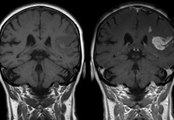

Just three nights of insufficient sleep raises the risk of a heart attack or stroke in those who are "perfectly healthy".